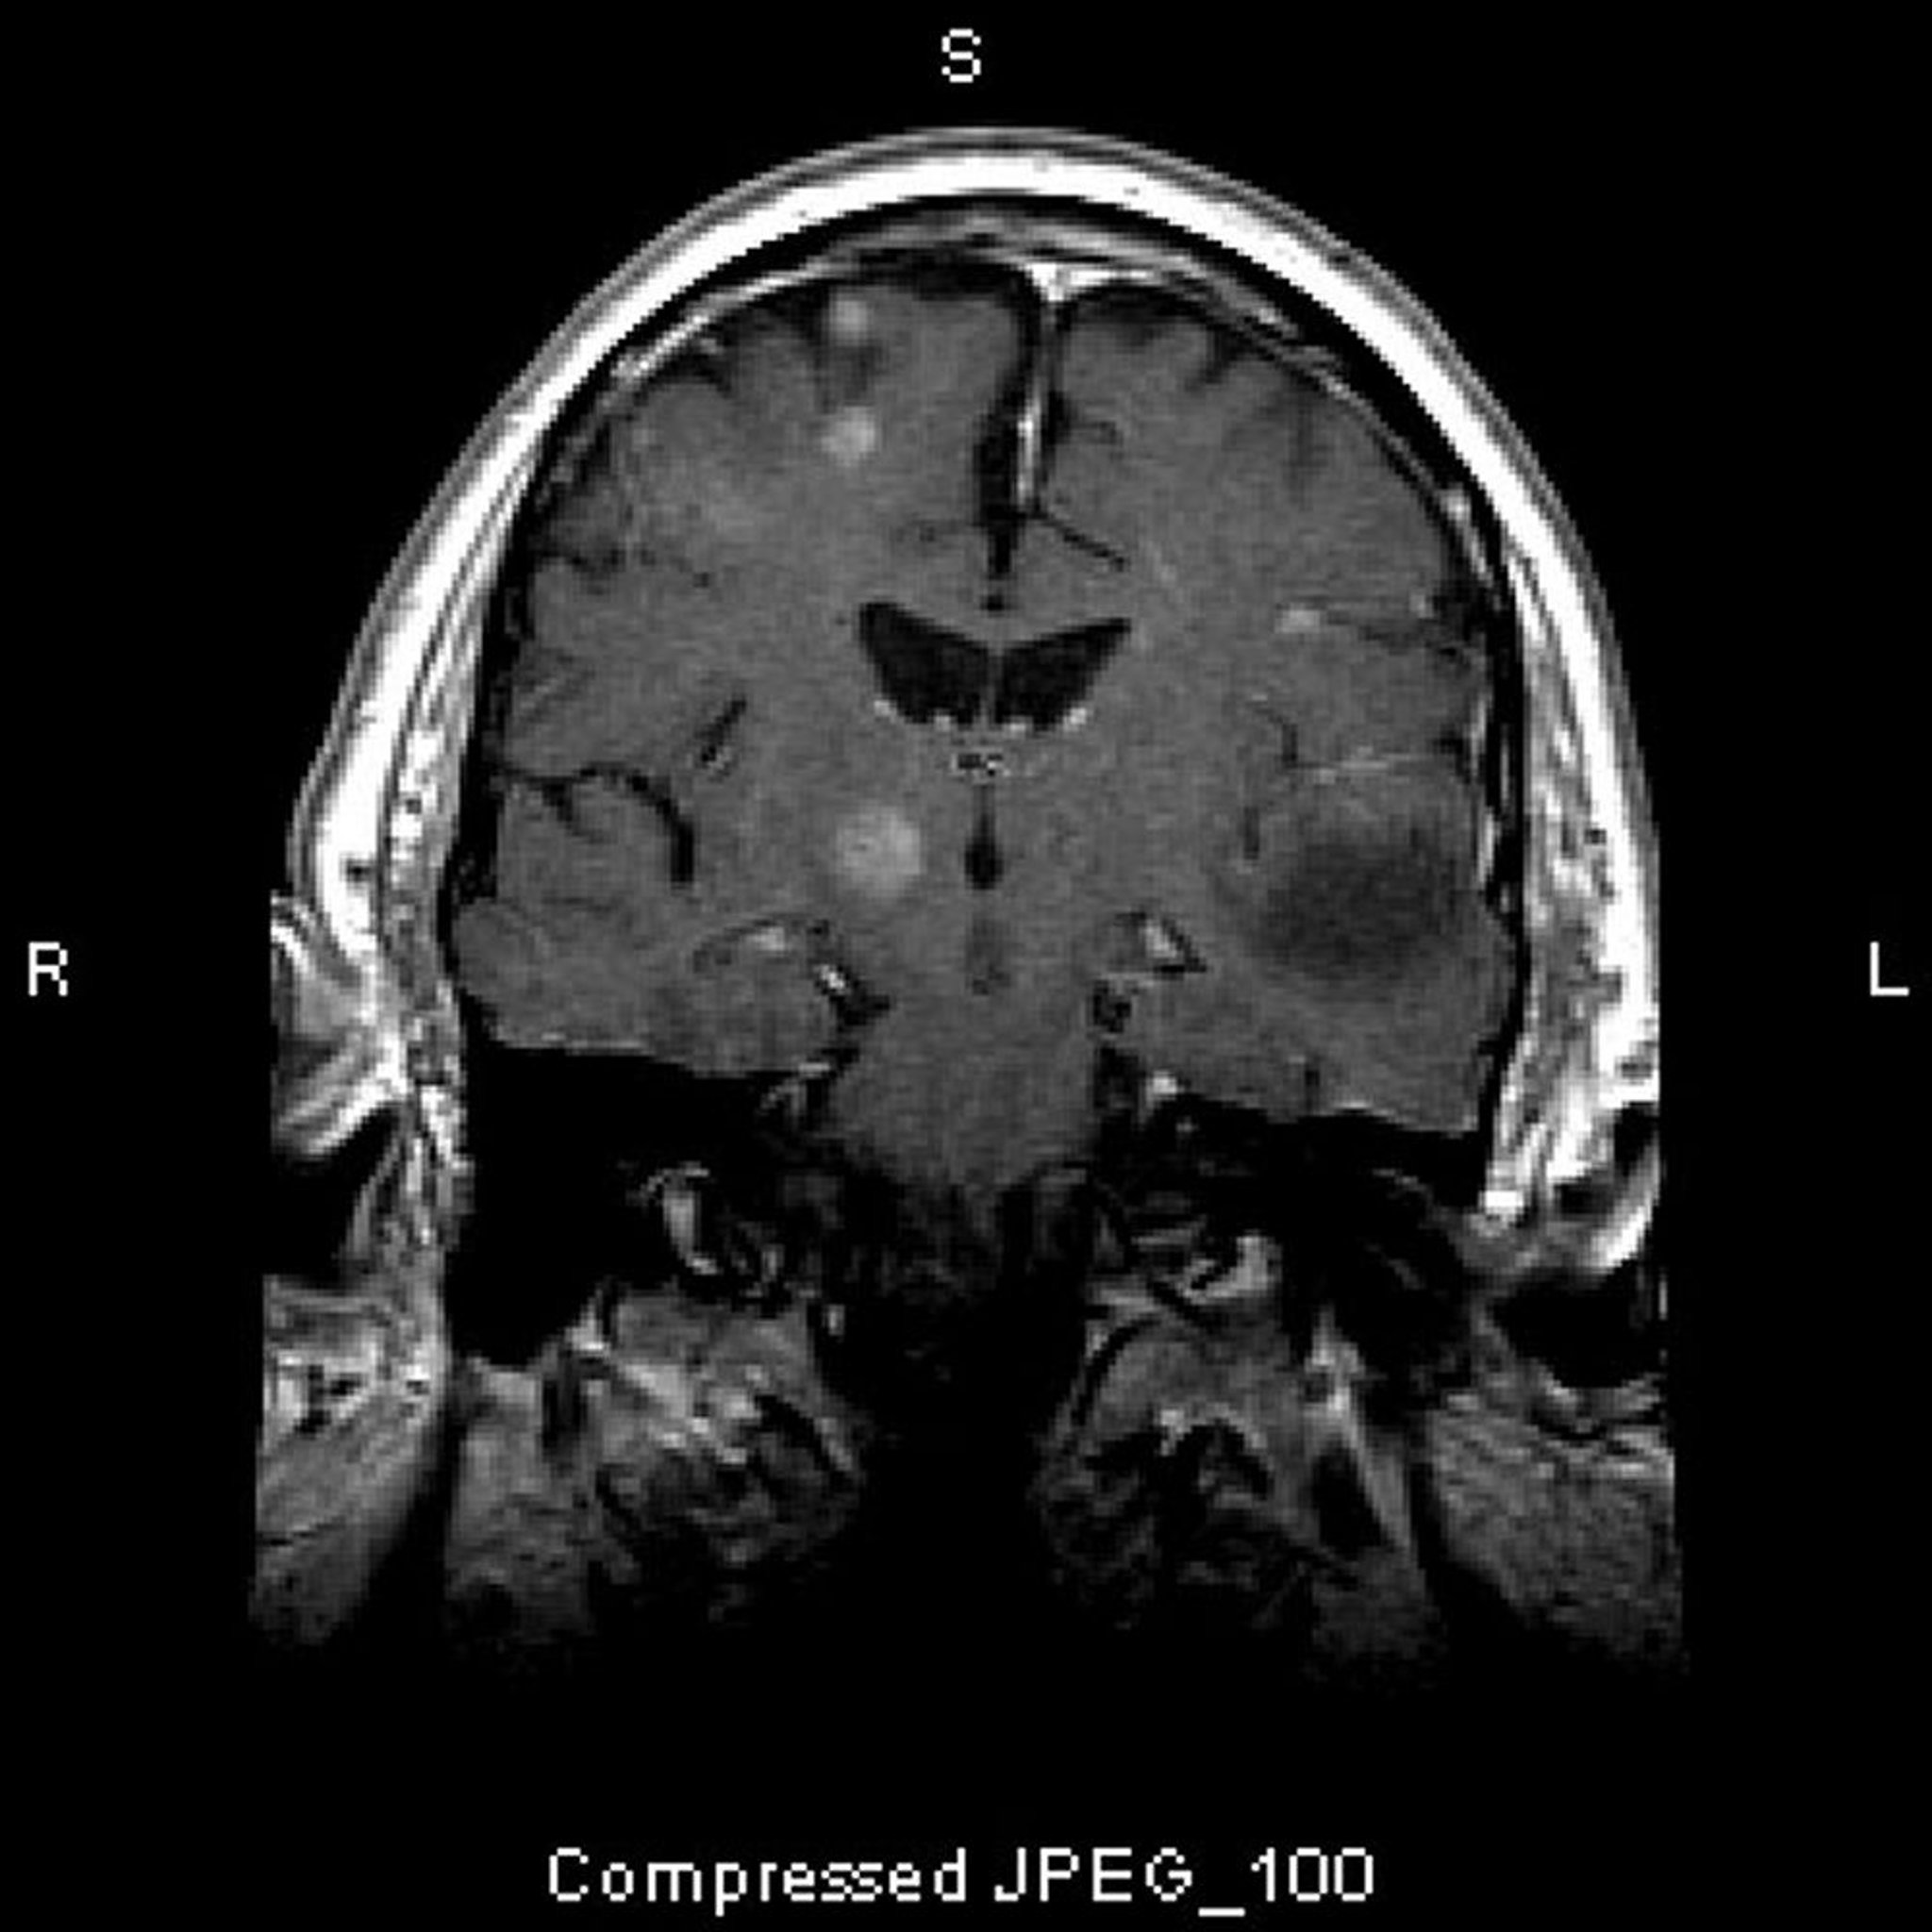

Di căn não

Chụp MRI này cho thấy nhiều tổn thương não, đại diện cho các khối u di căn. Trên 80% di căn não là đa di căn.

Hình ảnh do bác sĩ William R. Shapiro cung cấp